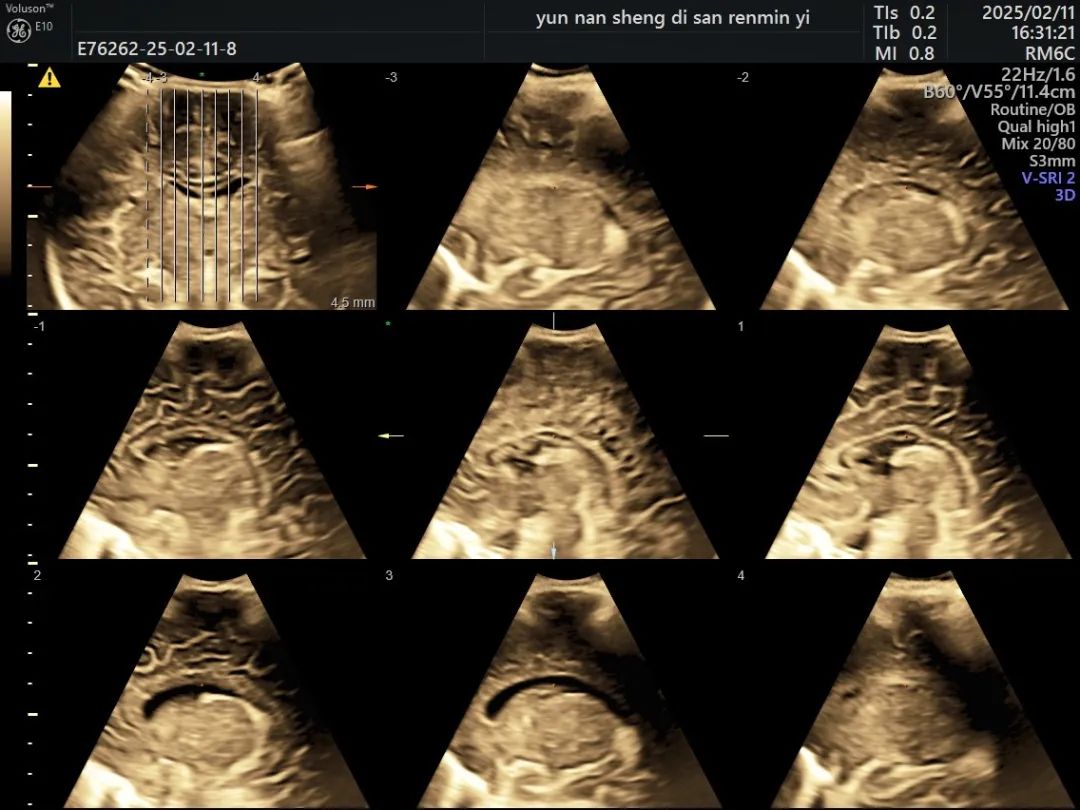

5. 三维成像:

三维超声能够立体化显示解剖结构,相比传统二维超声,提供更清晰的颅脑内部结构图像,检测范围广,减少操作时间,提高了效率。

(三维重建图像)

(脑表面三维成像)